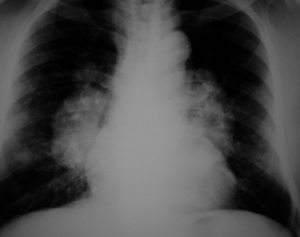

Sarcoidosis

- Abnormal collection of inflammatory cells (grandulomas) throughout the body.

- Most common location for granulomas to occur are the lung, skin, heart, and brain.

- Respiratory

- Due to pulmonary granulomata